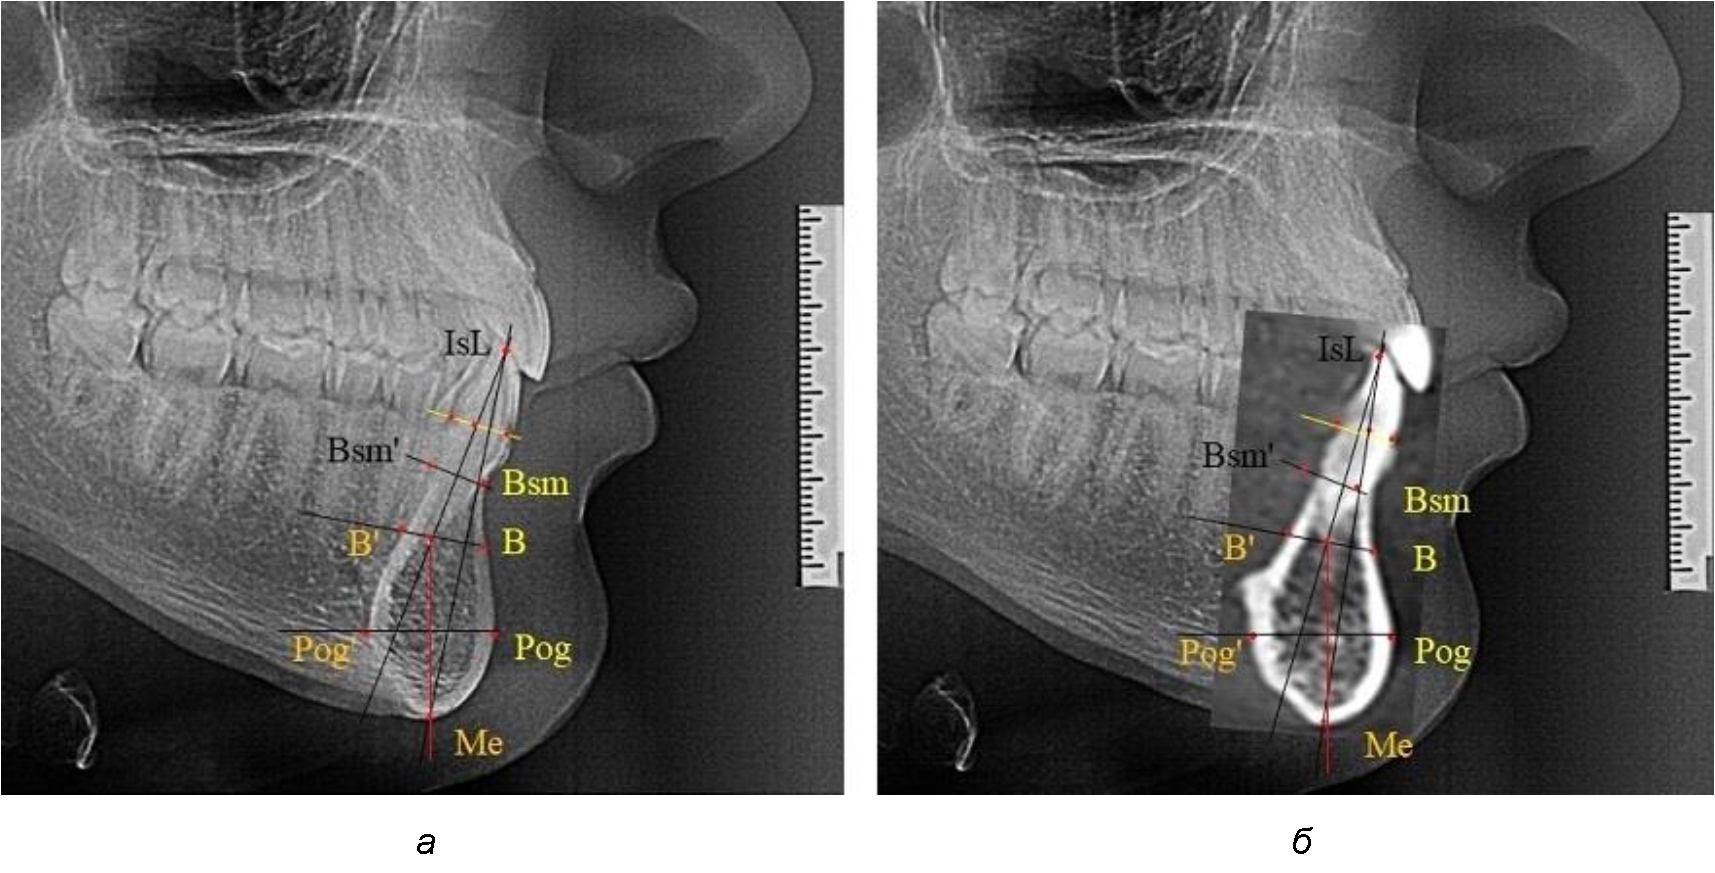

При необходимости и/или возможности проведения КЛКТ-исследования проводили анализ с сопоставлением фрагмента, что повышало точность диагностических мероприятий (рис. 2).

Рис. 2. Фрагменты ТРГ с ориентирами для измерения параметров резцового сегмента (а) и с наложением фрагмента КЛКТ (б)

Нередко отмечается деформация подбородочного выступа и различное его положение по отношению к зубоальвеолярной части сегмента. При мезиальной окклюзии нередко нижняя подбородочная точка смещается кзади по отношению к условной срединной вертикали нижнего резца, а при дистальной окклюзии отмечается компенсаторное отклонение подбородка кпереди (рис. 5).

Рис. 5. Особенности нижнечелюстного резцового сегмента на ТРГ у людей при мезиальной (а) и дистальной (б) окклюзии

Кроме того, так же как и у людей с физиологической окклюзией, определялось различие в положении апикальных точек Downs и Schwarz, что, по нашему мнению, может определять тактику лечения патологических форм протрузии/ретрузии резцов с учетом биотипа костной ткани.